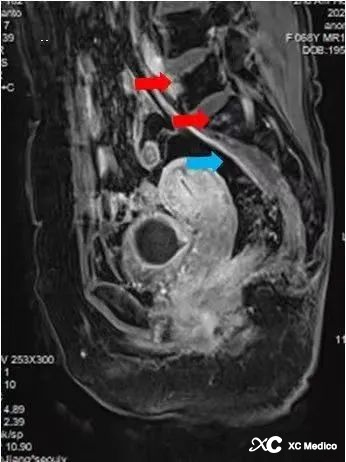

Примечание: обширный остеопороз поясничного и крестцового таза. Разрушение антеросочериорного края поясничных 5 позвонков со склеротической гиперплазией края (показанная красной стрелкой). Прилегающая гиперплазия рубцов. Разрушение левого сакровистой суставы с разрушением боковой суставной поверхности подвздошного подвздошного ткани, множественными внутренними мертвыми костями и локализованной гиперплазией тканей, похожей на рубцов (показано синими стрелками).

Примечание. Увеличенная MR: поясничная 4/5 выпуклость диска с остеофитами позвоночного обода, гипертрофия флавума лигаментума, небольшое сужение позвоночного канала и сжатие переднего края дурального мешка. Тело поясничного 5 позвонка ограничено вогнутым и может рассматриваться как полоски длинного T1 и T2 Wi Compression High Signal, а усиление наблюдается после усиления. Множественные участки аномального сигнала наблюдаются под конечными пластинами поясничного отдела 5 и сакральных 1 и под крестцовых суставов, с низким сигналом на T1WI и слегка высоким сигналом на T2WI, а усиление наблюдается при сканировании улучшения (красные стрелки). Было замечено утолщение мягких тканей на переднем крае крестцовых позвонков, а при усиленном сканировании наблюдалось усиление (синяя стрелка). Костные сигналы подвздошной кости, бедра, крестца и бедренной головы на обеих сторонах таза не показали никакой очевидной аномалии, и сигналы внутренних и внешних мышц таза были нормальными, с чистыми мышцами и нормальными разрывами суставов без признаков. расширения и сужения.